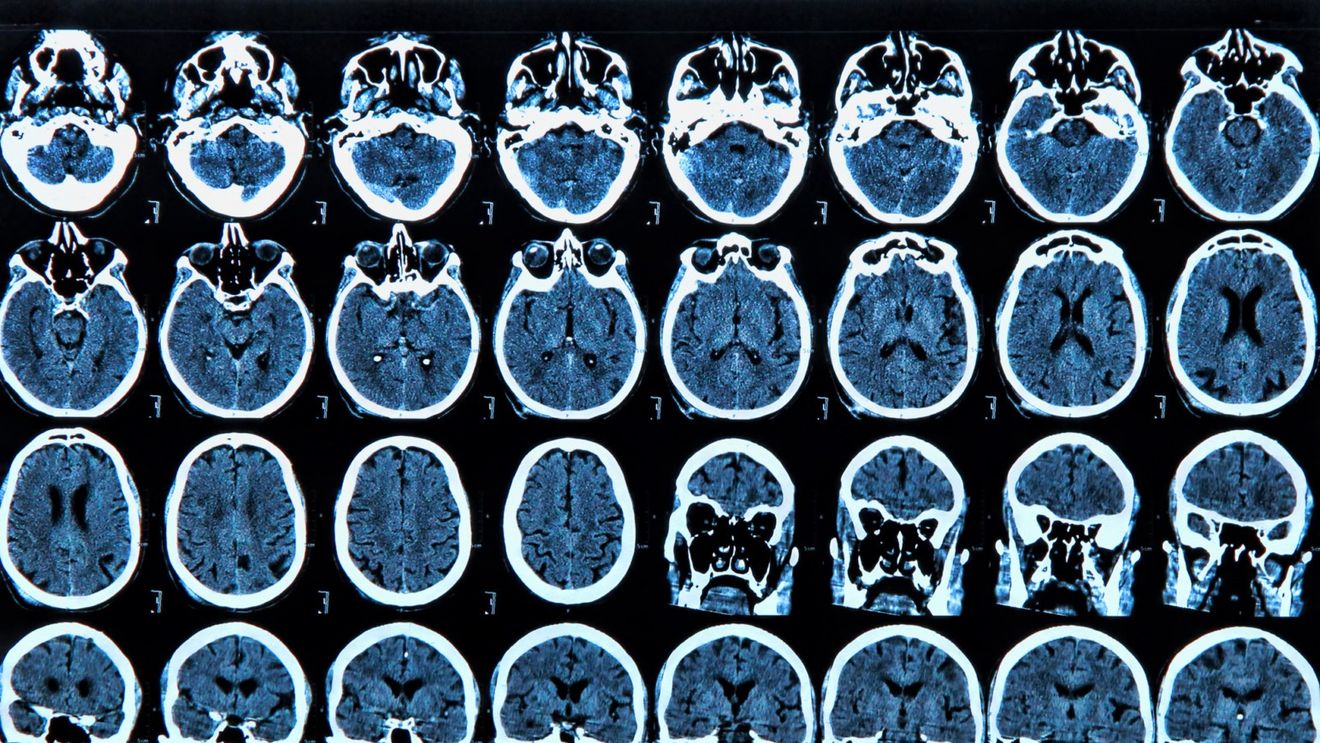

Cercetătorii din Australia au descoperit că boala Parkinson provoacă modificări semnificative şi progresive ale vaselor sangvine cerebrale, schimbând modul în care această boală este înţeleasă, ceea ce ar putea să ducă la noi căi de tratament, informează marţi agenţia de presă Xinhua, citată de Agerpres.

Deşi boala Parkinson este caracterizată prin depuneri de proteine alfa-sinucleină, această cercetare a schimbat înţelegerea asupra bolii, demonstrând că modificările specifice regiunii vaselor de sânge din creier stau la baza progresiei bolii, a anunţat marţi Neuroscience Research Australia (NeuRA) din Sydney într-un comunicat de presă.

„Cercetările noastre au identificat modificări specifice regiunii în vasele de sânge ale creierului, inclusiv o prezenţă crescută a vaselor filiforme, care sunt resturi nefuncţionale ale capilarelor”, a mai spus Derya Dik.

Cercetătorii de la NeuRA, în colaborare cu Universitatea din New South Wales şi Universitatea din Sydney, au observat, de asemenea, modificări legate de modul în care sângele curge în creier şi de modul în care funcţionează bariera hematoencefalică, potrivit concluziilor studiului, publicate în revista Brain.